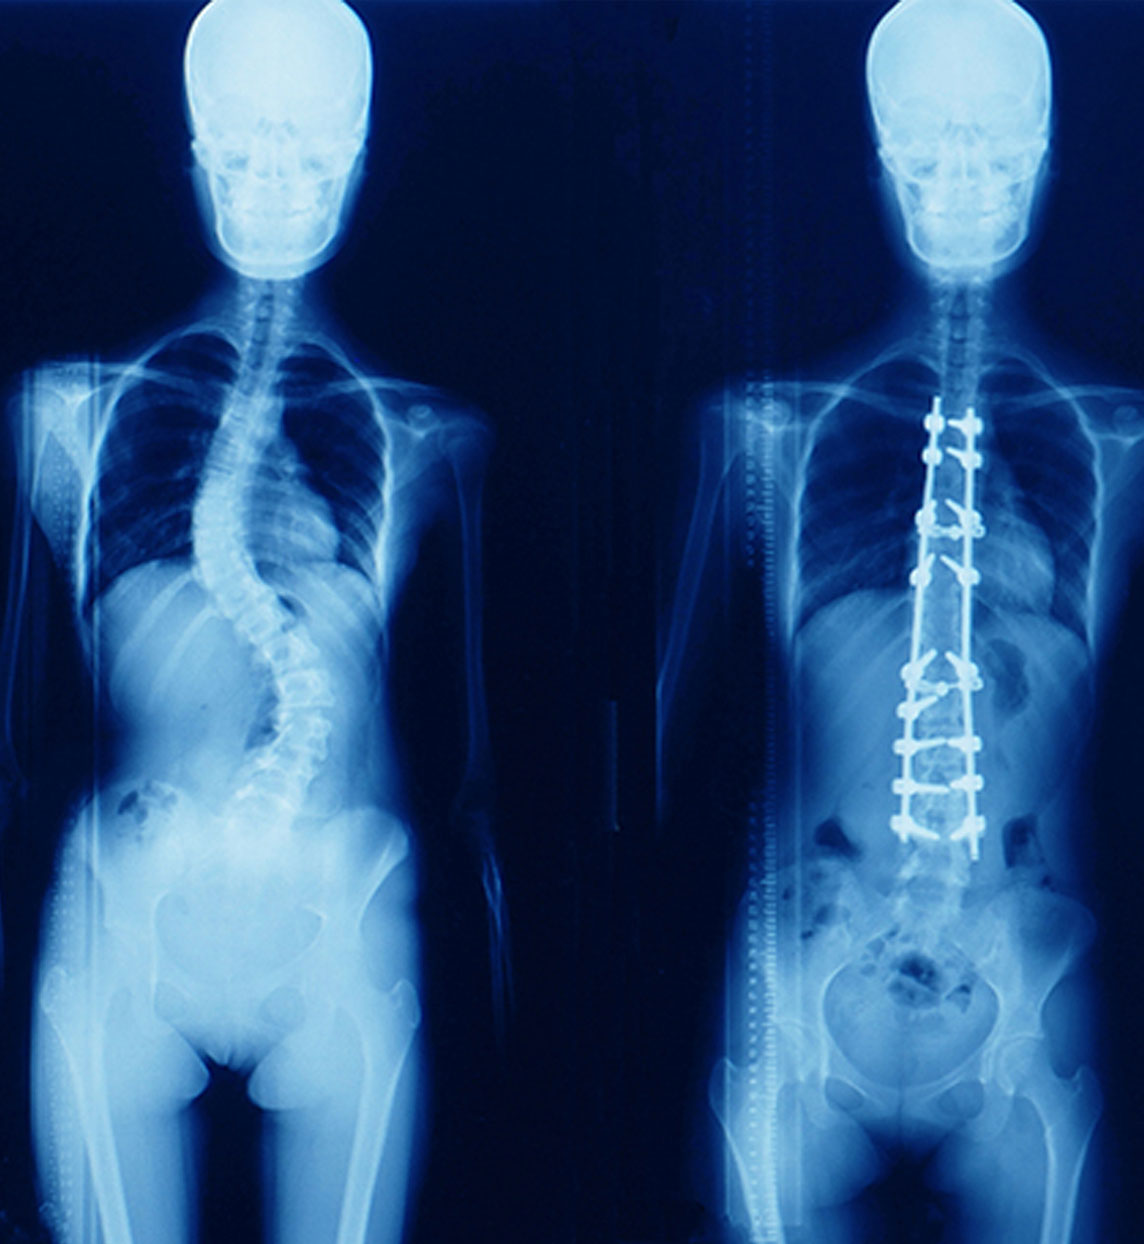

CIRUGÍA DE ESCOLIOSIS

Realizar una cirugía de escoliosis lleva varias horas por su complejidad, la hospitalización es prolongada y algunas actividades estarán restringidas por varios meses; pero tiene un alto porcentaje de éxito en detener y corregir la deformidad de la columna vertebral.

Si se sospecha escoliosis será necesario examinar la espalda. Se solicitaran radiografías para confirmar el diagnóstico y para medir el grado de deformidad que presenta.

E.B. 16 años, lo diagnosticamos con Escoliosis Ideopática Juvenil y su operación duró 7 horas. Él fue uno de nuestros casos complejos de escoliosis tratados con éxito.